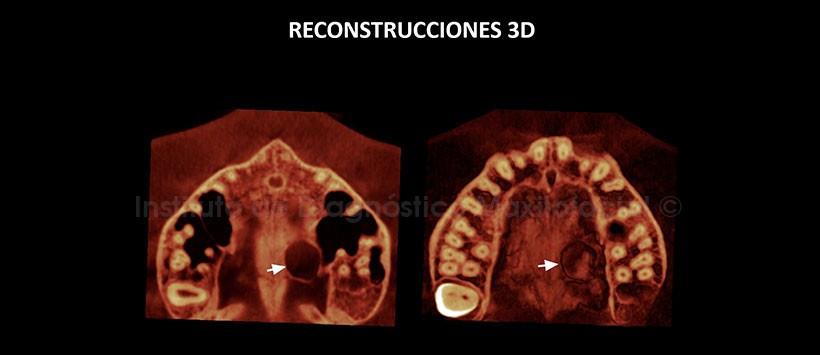

En las reconstrucciones 3D (Figuras 4 y 5) se aprecia la lesión antes descritas.